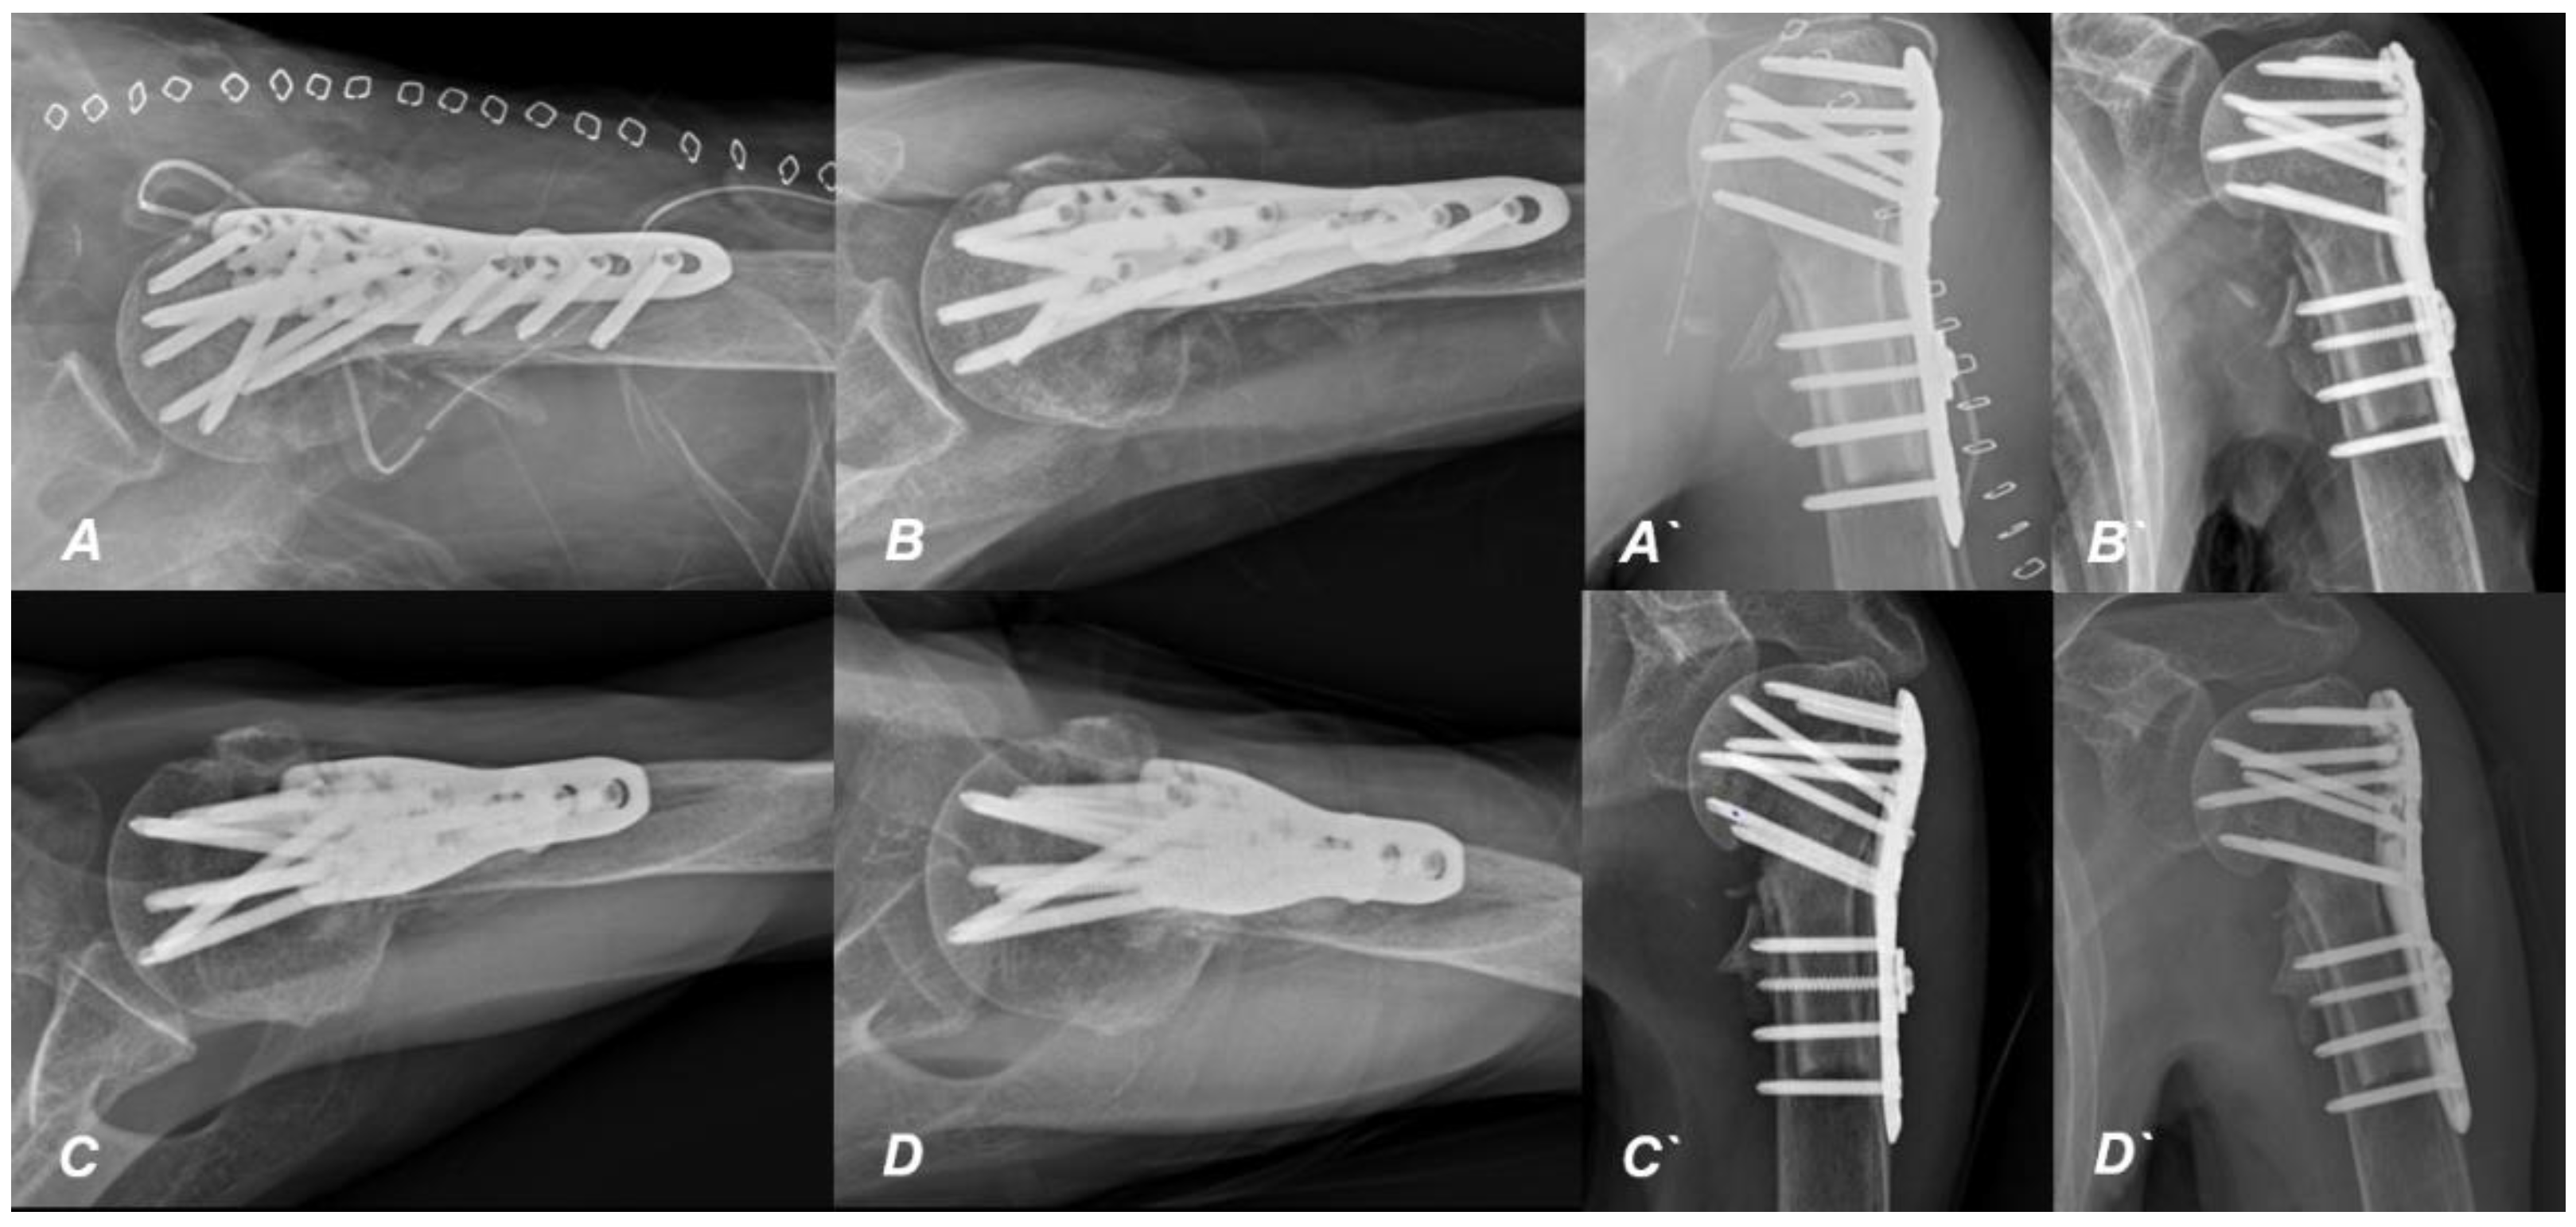

2. Case Presentation

Surgical Technique